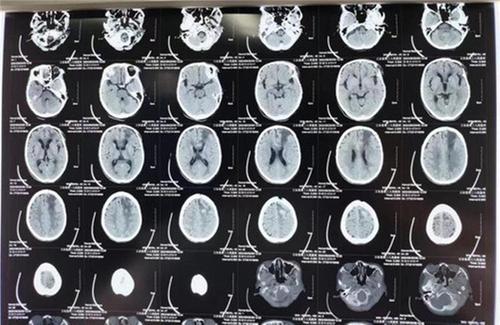

(出院復(fù)查CT示:左側(cè)額葉及胼胝體膝部片狀低密度影)

顱腦外科手術(shù)后意識(shí)恢復(fù)是成功的第一步,但行動(dòng)、思維、語(yǔ)言等功能和社會(huì)適應(yīng)能力的恢復(fù)還有很長(zhǎng)的路要走。陳婆婆生病以來(lái),右側(cè)肢體的肌力0~1級(jí),能否恢復(fù)到生活自理、行動(dòng)自如的狀態(tài)取決于她腦功能的恢復(fù)與功能康復(fù)促進(jìn)效果。為此,神經(jīng)外科在患者意識(shí)恢復(fù)后立即組織康復(fù)科、神經(jīng)內(nèi)科、護(hù)理部多學(xué)科聯(lián)合會(huì)診,制定康復(fù)促進(jìn)方案。康復(fù)團(tuán)隊(duì)?wèi)?yīng)用上下肢綜合訓(xùn)練、肌力訓(xùn)練、推拿、針灸理療等現(xiàn)代康復(fù)方式,患者、家屬、康復(fù)師通力協(xié)作,僅15天患者右側(cè)肢體肌力便逐漸恢復(fù)至4級(jí),能夠在單手助力攙扶下行走和拿起物件,基本恢復(fù)了正常生活能力。